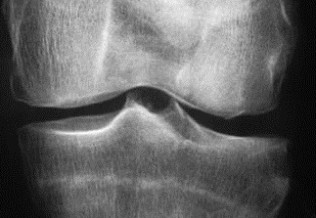

Arthroses digitales érosives : un effet structural potentiel du méthotrexate